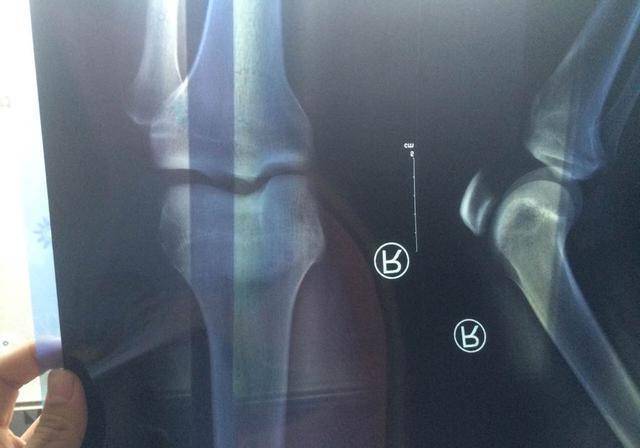

不过最近洋洋家阴云密布,原因是杨洋在一次体检中被诊断为停止发育。要知道洋洋今年才14岁,他从小就长得快,就算这两年身高增长没有那么迅猛被同龄的孩子追平,可这样就是停止发育了嘛?

不甘心的家长又到更加权威的意愿给孩子做了检查,检查结果一样,骨骺闭合停止发育。怎么会这样呢?严格为孩子选择有营养的食谱一直都是家人生活中的一点小得意啊?

不过营养过剩就是导致孩子停止发育的罪魁祸首之一。过量的钙质以及营养物质补充让骨头生长区加速钙化,看起来好像是比同龄的孩子长得快,实则是牺牲了以后更多的可能性。